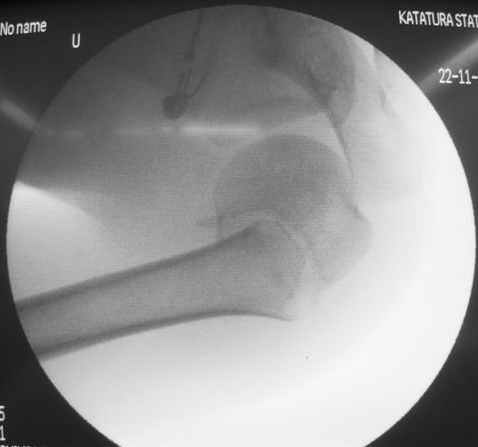

Клинические снимки - 3 недели после операции

Evgueny Tschekashkin 02 Декабрь 2004, 01:26

Посылаю послеоперационные Рг граммы.

Отправитель: Alexander Chelnokov 02 Декабрь 2004, 19:21

Поздравляю, получилось просто замечательно. Если можно, расскажи чуть подробнее, как делали - как вправляли, как вводили спицы, поворачивали ли их?

Я и сам доволен результатом. В предпоследнем письме я кратко описал ход операции - закрыто репонировать не удалось( 2 недели с момента травмы и 1 неделя после неудачной репозиции) после удаления пучков спиц, пришлось сделать - 2см разрез на уровне перелома и с помощью периостального элеватора (золотое правило механики) *одеть* головку на дистальный отломок.

Спицы проводил через старые отверстия, вращая пучок импактором- направителем при его введении в головку.